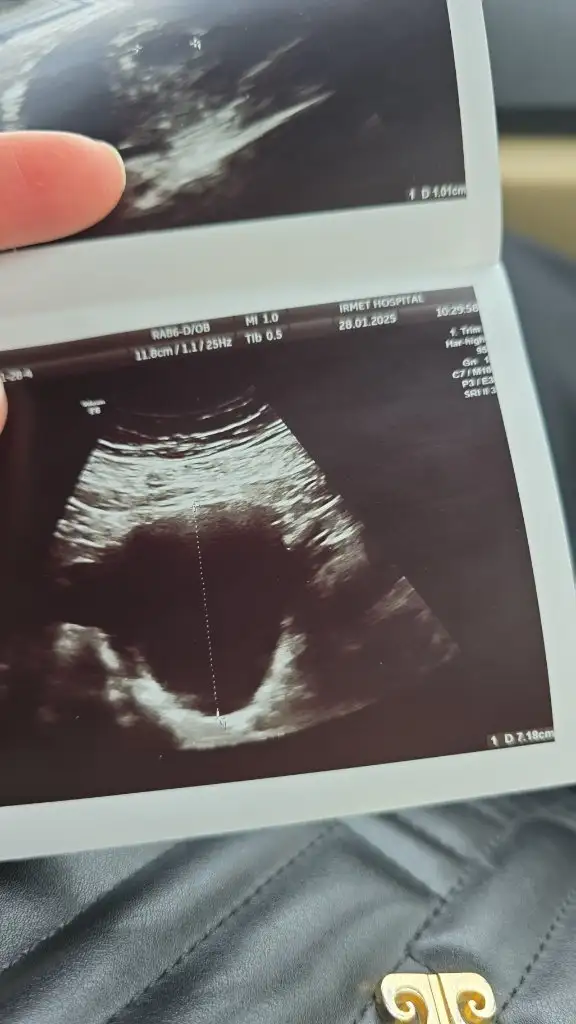

Benim de sat 27 Aralık

28 ocakta beta 202

30 Ocak beta 561

Doktor yükselme iyi tekrar kan baktırmaya gerek yok ama isterseniz 2 gün sonra tekrar baktırın dedi

8 Şubatta randevum var bakalım keseyi görebilecek miyiz acaba siz epey erken görmüşsünüz maşallah

• IMG-20250128-WA0001.webp

30,7 KB · Görüntüleme: 850